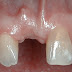

Mất răng không những làm cho việc ăn uống trở nên khó khăn mà tính thẩm mỹ và sức khỏe tổng quát của cơ thể cũng bị ảnh hưởng vì thế nhanh chóng phục hình răng đã mất là điều bạn cần thực hiện nay ngay. Vậy giải pháp nào tốt nhất để phục hình răng đã mất hiệu quả an toàn ? Hãy tham khảo bài viết dưới đây để có những thông tin hữu ích nhé!

Có rất nhiều nguyên nhân gây ra tình trạng mất răng như:

– Mắc những bệnh về răng: sâu răng không có giải pháp điều trị kịp thời, bệnh nha chu không được chữa trị, viêm nướu, viêm chân răng,…

– Răng mọc lệch gây ảnh hưởng đến các răng còn lại và bạn cần phải nhổ

– Những chấn thương vùng hàm mặt: do tai nạn làm gãy răng và mất răng

– Một vài trường hợp do bẩm sinh.